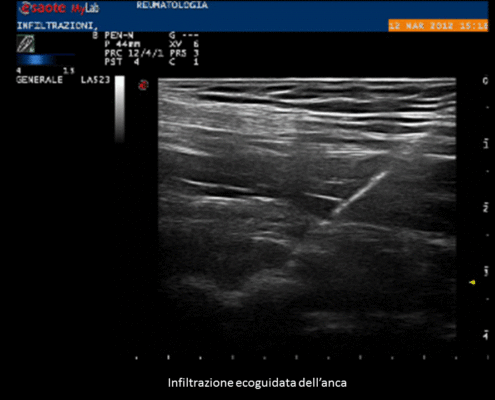

Sempre recentemente è stato ampiamente dimostrato che, soprattutto per le articolazioni profonde, risulta molto difficile andare a posizionare l’ago e quindi il farmaco nella zona giusta, per cui si è fatto sempre più strada il concetto che le infiltrazioni necessitano di una guida ecografica.

Ciò è particolarmente vero per l’anca, dove si è visto che senza guida ecografica solo una minima parte delle infiltrazioni arriva realmente a destinazione.

Le procedure ecoguidate, oltre a garantire un corretto raggiungimento della struttura bersaglio, permettono di creare minor discomfort al paziente e di evitare di colpire strutture nobili durante il tragitto dell’ago. Ovviamente per l’esecuzione di tali procedure è necessario una buona esperienza sia nell’ambito dell’ecografia muscoloscheletrica che in quello delle procedure infiltrative, oltre ad una estrema attenzione al corretto mantenimento di sterilità durante l’operazione.